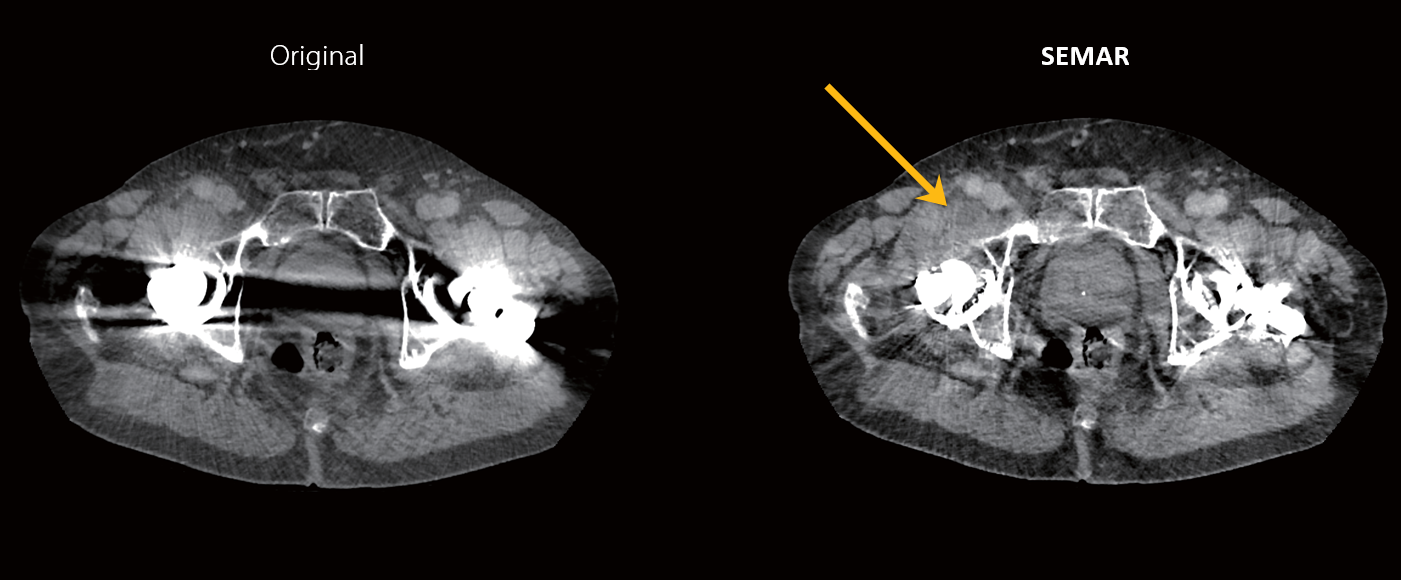

Візуалізація гематоми з SEMAR (приклад дослідження)

73-річний чоловік скаржився на постійний біль у правій паховій ділянці після заміни кульшового суглоба 3 місяці тому. Пацієнта направили на комп’ютерну томографію черевної порожнини та малого тазу після того, як інші методи візуалізації, включаючи звичайний рентген та ультразвукове дослідження, не змогли визначити причину болю.

Післяопераційну гематому було виявленно в правій області паху (стрілка) і було краще видно на зображеннях реконструкції Single Energy Metal Artifact Reduction (SEMAR). Інші сусідні структури, такі як простата, краще візуалізуються на реконструкції SEMAR.

Реконструкція з SEMAR дозволяє знизити артефакти від металу, що дозволяє діагностувати патологію, що не візуалізується під час звичайної КТ-реконструкції.